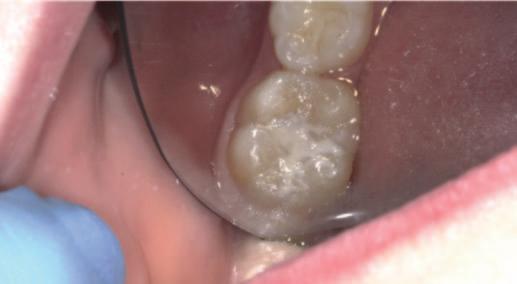

FIGURE 1: Hypomineralised mandibular right first permanent molar with early post-eruptive breakdown – suitable for a GI sealant. Natasha Lemasney BA BDentSc MFD RCSI MSc Senior House Officer, Paediatric Dentistry Cork University Dental School and Hospital Siobhán Lucey BDS NUI MFDS

Finally, in instances of MIH, GI may be considered the first-line sealant material (Figure 1).3 Placing a resin-based sealant on a sensitive tooth may be distressing for a child and may increase the risk of treatment-induced anxiety. Even though the retention rates for GI sealants are reduced compared to those of resin-based sealants, studies have shown that small amounts of material remain in the pits and fissures even after the sealants appear to have debonded.4